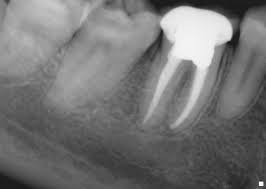

An X-ray is taken initially to fully understand the shape of the root canal and to check for infection in and around the affected area of the tooth.

Dentist after making sure that the infection has been cleared fills the interior of the tooth with a paste at the root and finally inserts filling into the hole drilled initially to get to the root.

Finally the tooth is filed and shaped up to fix a ceramic cap or any other type of dental crown. This prevents further infection to the tooth by the wearing down of the filling inside the tooth.

root canal treatment steps